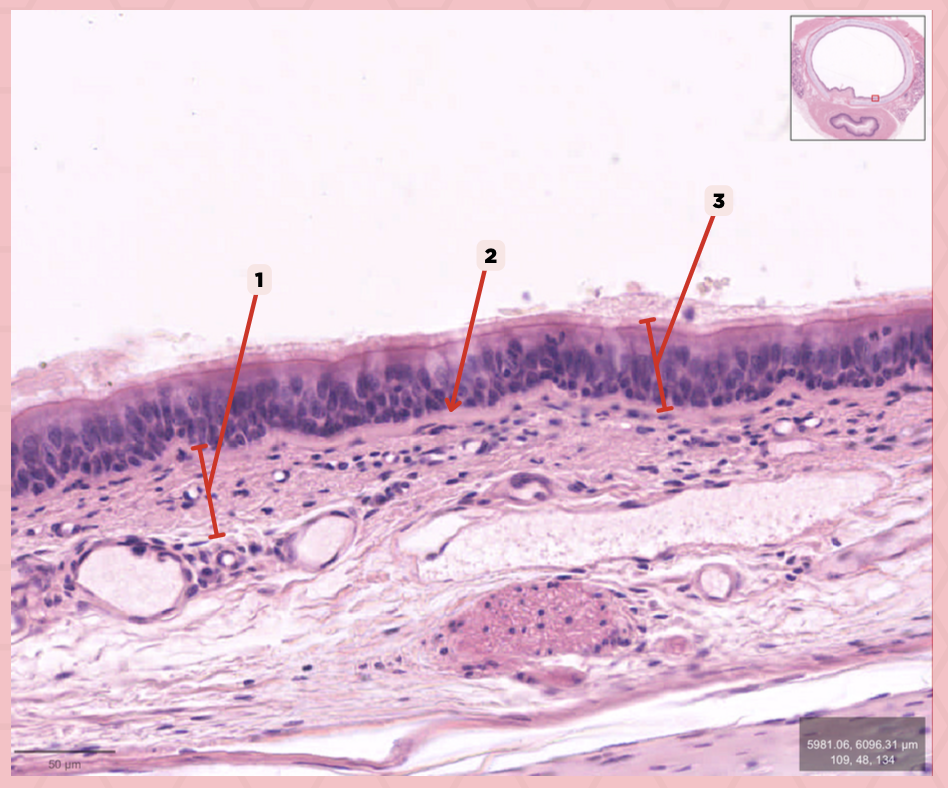

Respiratory Epithelium

Identify the structure labeled as 1.

Lamina Propria

Identify the structure labeled as 2.

Bony spicule

Identify the structure labeled as 3.